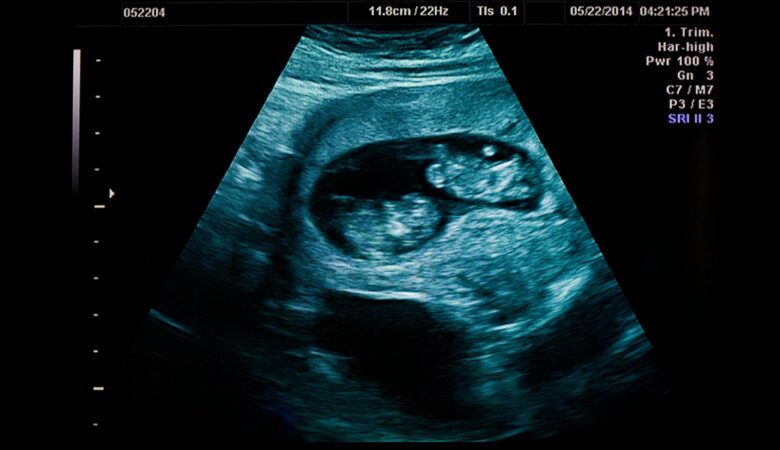

While these apps may not replace traditional medical ultrasounds performed by professionals, they can be incredibly useful in certain situations. Imagine being able to quickly assess injuries during sporting events or monitor pregnancy progress from the comfort of your own home. However, it’s important to note that these apps should always be used in conjunction with proper medical advice and consultation.

To create an ultrasound image, the app emits high-frequency sound waves into the body. These waves travel through the tissues and bounce back when they encounter different structures such as organs or bones. The app’s software analyzes the returning waves, measuring the time it takes for them to return and their intensity. This information is then used to generate a visual representation of the scanned area.